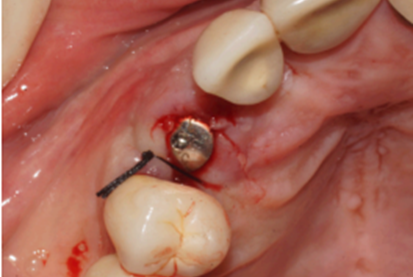

Figura 12 – Pilar Ideale de 3.3 X 4.0 X 1.5 de 17° instalado

Após 90 dias da instalação do implante, o cicatrizador foi removido e fazendo uso do Kit de Seleção de Componentes da mesma empresa, foi selecionado um pilar Ideale angulado de 3.3 X 4.0 X 1.5 de 17°. Essas mediadas se referem ao diâmetro, altura protética, altura do transmucoso e ao ângulo do pilar, respectivamente (Figuras 9, 10 e 11).

Uma vez selecionado, o pilar Ideale foi instalado e torqueado a 20 Ncm como recomendado pelo fabricante (Figura 12). Nessa mesma consulta foi colocado sobre o pilar Ideale um transferente digital referente ao mesmo e as arcadas foram escaneadas (Figuras 13, 14 e 15).